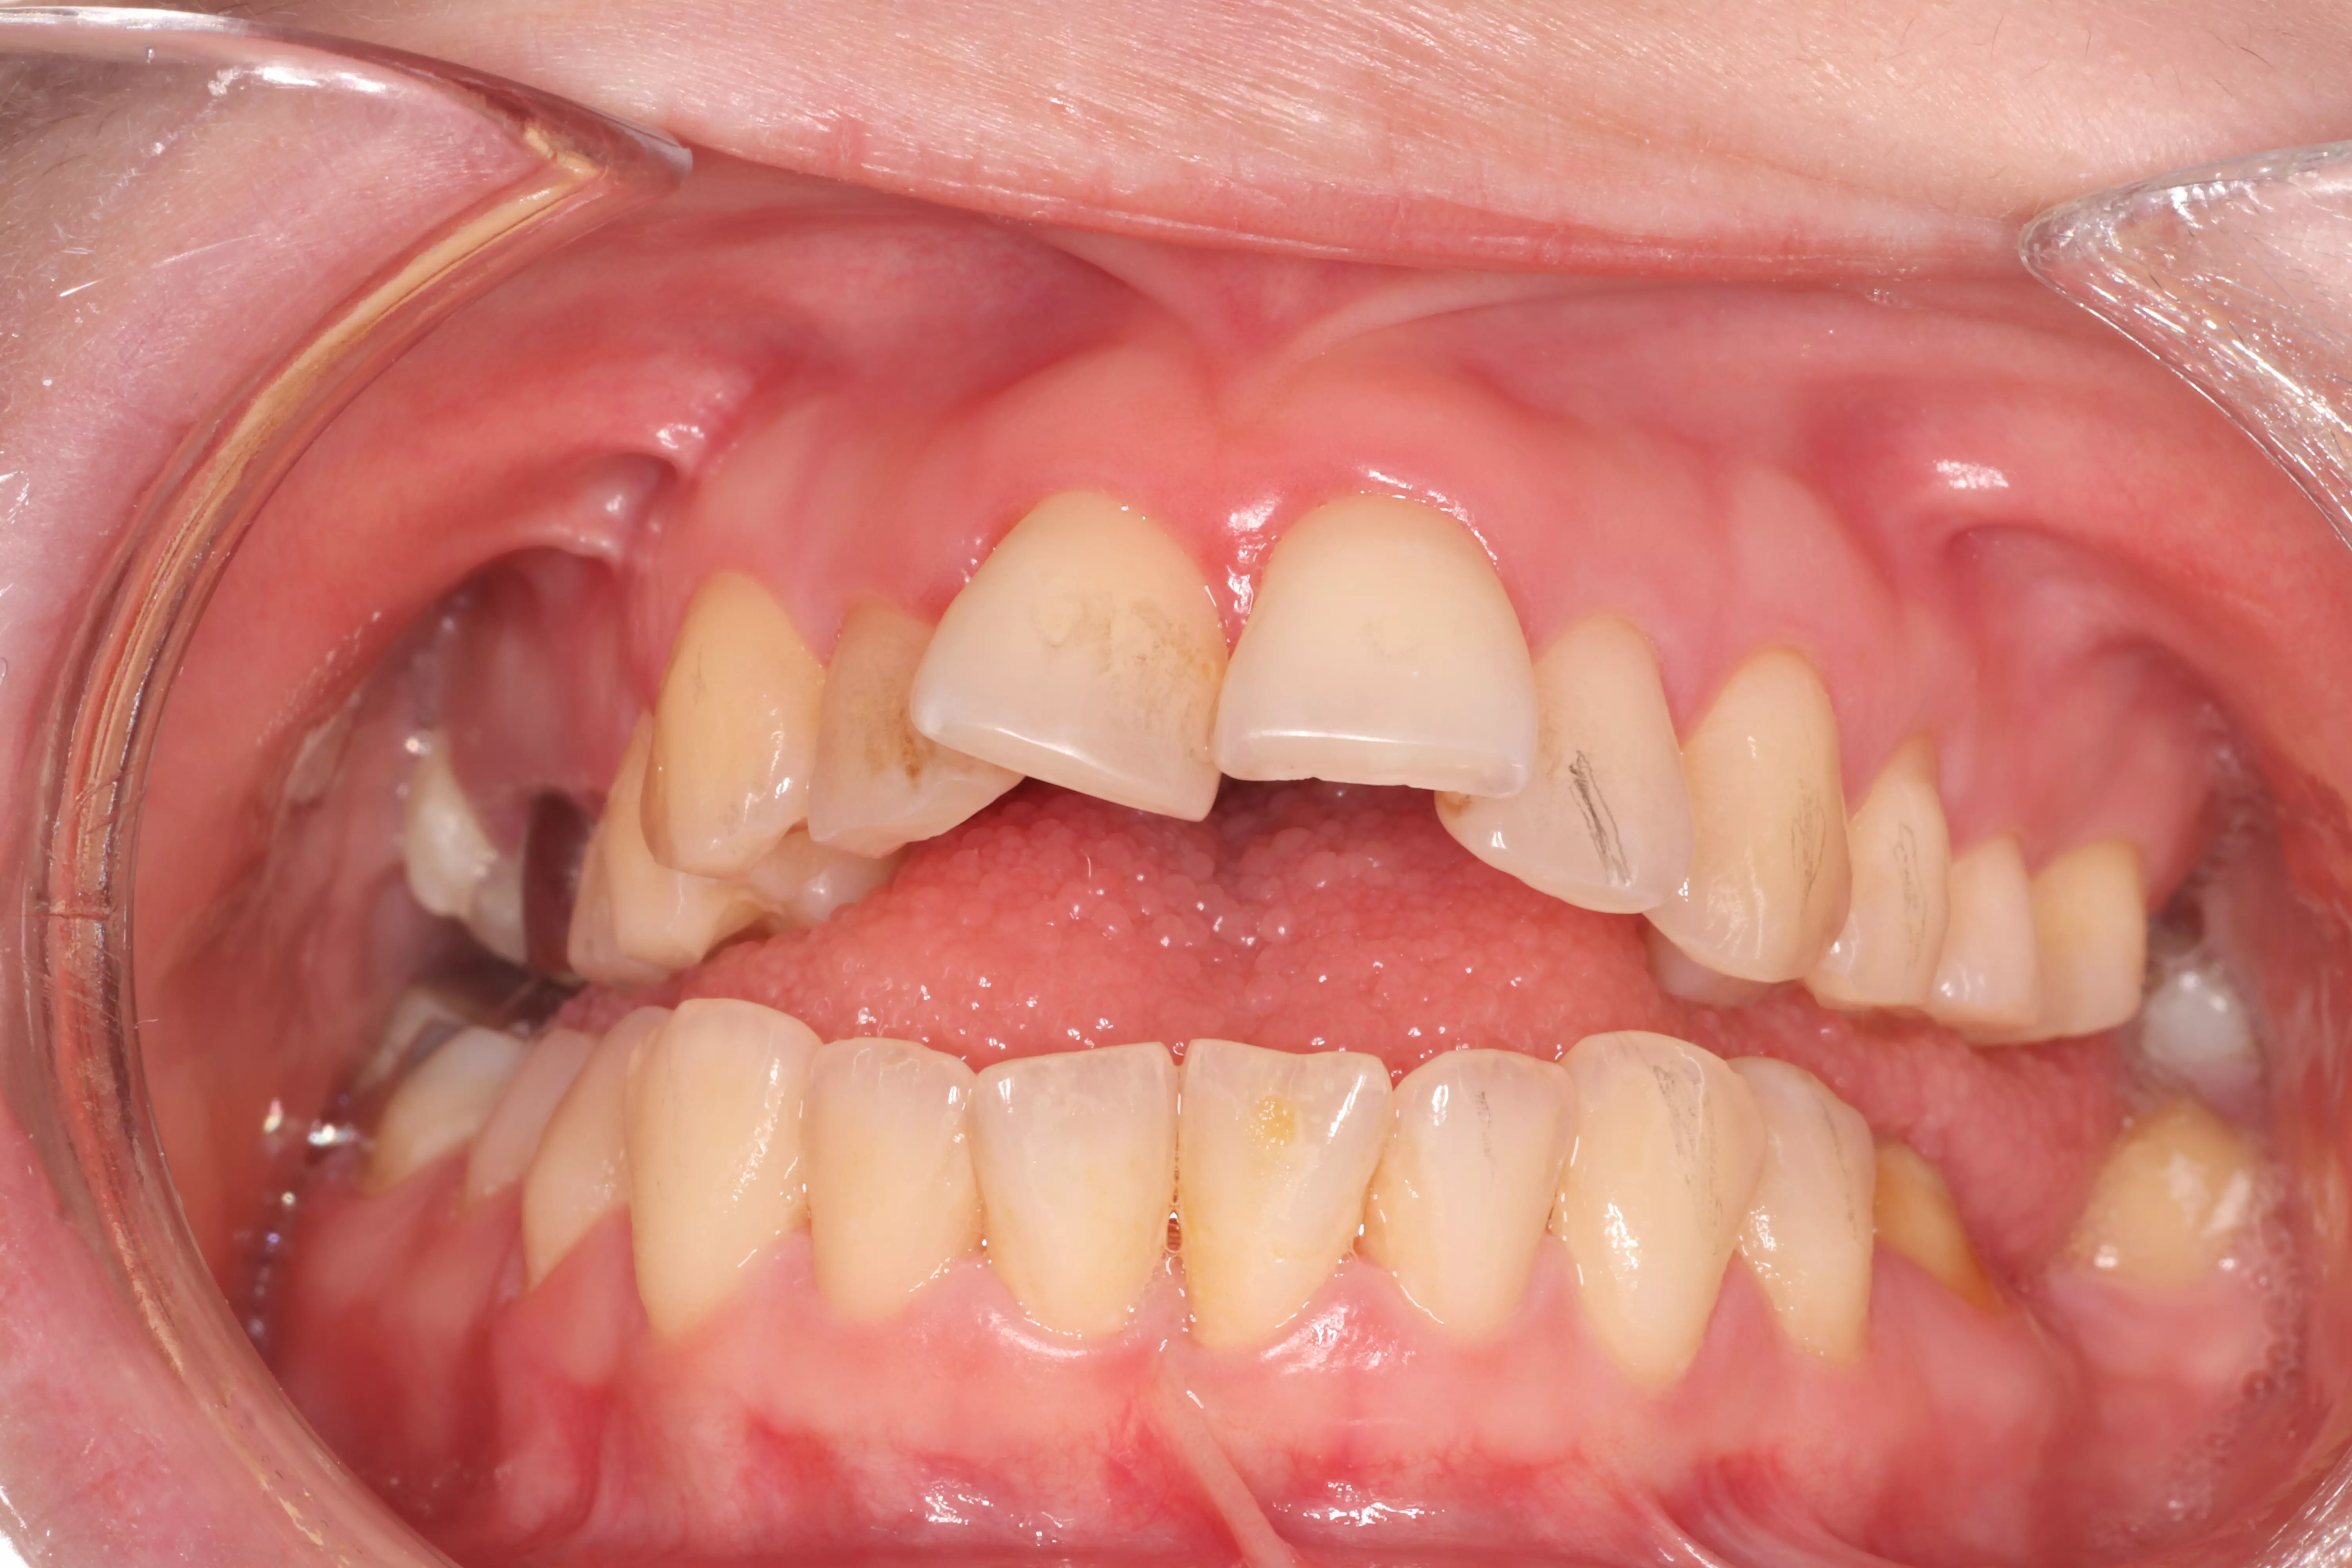

下方是患者初診的照片。患者有嚴重的咬合不正,但是基於身體條件,不適合進行齒顎矯正。下顎左側的缺牙使得她原本就不好的咬合功能變得雪上加霜,吃東西變得更困難。

下方是治療完成的照片。歷時四個多月,在患者、家屬、及醫療團隊的共同努力下,終於完成新的假牙製作。